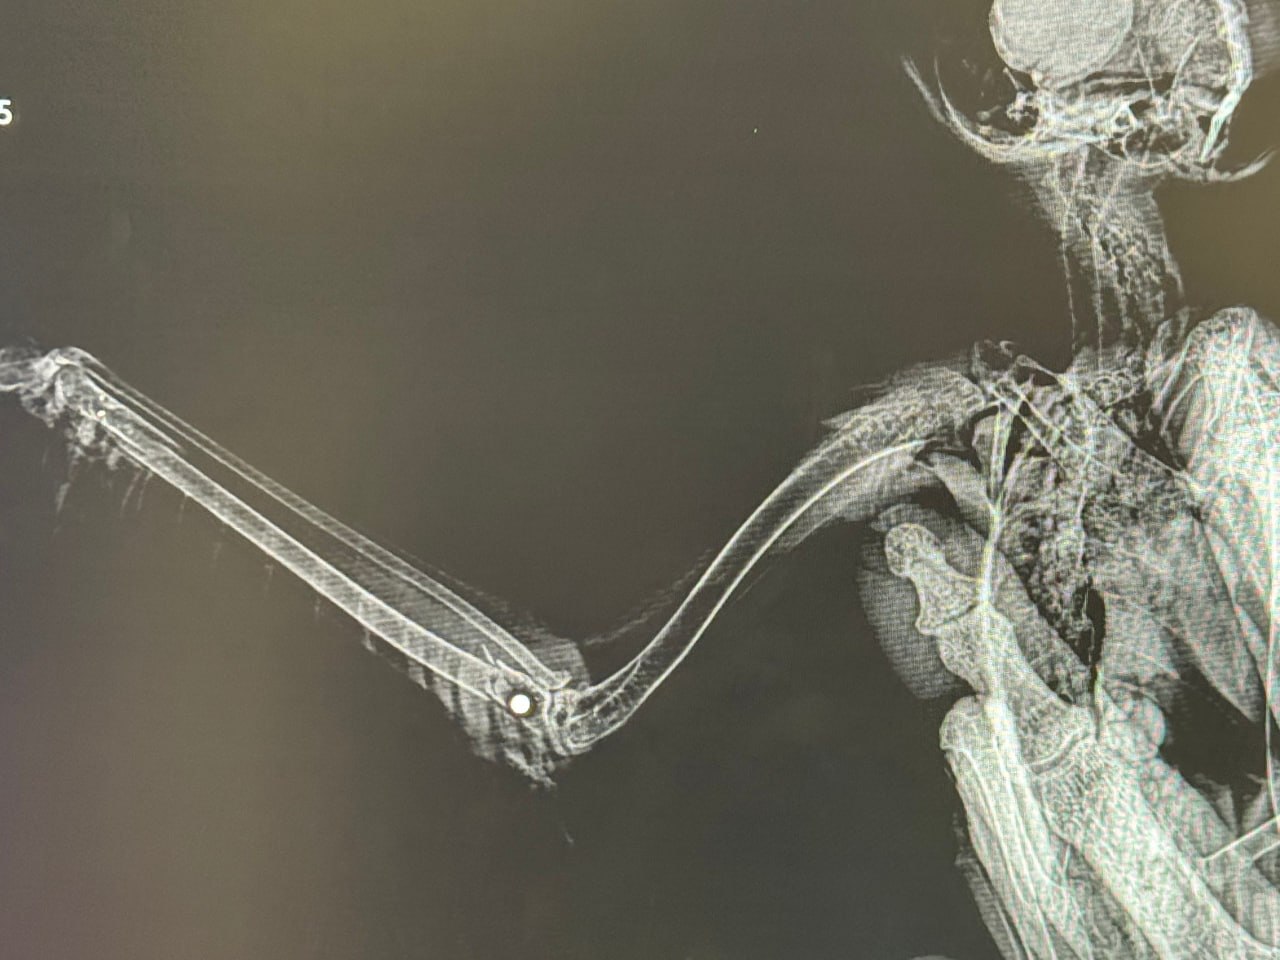

— У обеих сов множественные страшные травмы от поражения дробью. У первой раздроблен запястный сустав и бедренная кость. Одна из дробин засела прямо внутри кости. У второй раздроблены обе лапы, перебиты локтевая и лучевая кости, в теле множественные мелкие осколки дроби, — отметили специалисты.

Они добавили, что внутренние органы у птиц не повреждены, однако их состояние оценивается как тяжёлое из-за полученных травм, кровопотери и истощения.